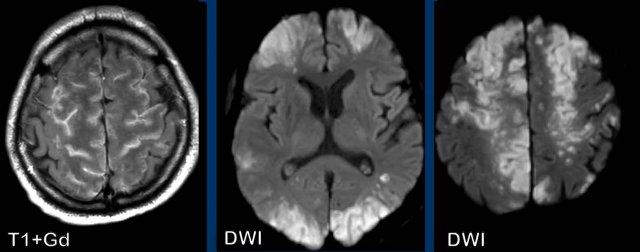

Đây là bệnh nhân nhiễm COVID, biến chứng bởi rối loạn đông máu dẫn đến nhồi máu não đa ổ.

Lưu ý kiểu ngấm thuốc dạng hồi não.

Tiếp tục xem thêm hình ảnh của bệnh nhân này…

Một lần nữa, hãy lưu ý hình ảnh ngấm thuốc dạng hồi não trên chuỗi xung T1W+Gd do hiện tượng tưới máu xa xỉ, đồng thời lưu ý hình ảnh hạn chế khuếch tán lan rộng trên chuỗi xung DWI.

Bạn có thể xác định những vùng mạch máu nào bị tổn thương không?

Các vùng này được gọi là vùng phân thủy (watershed) hay vùng ranh giới mạch máu (border zone).

Vùng ranh giới mạch máu nhận nguồn cung cấp máu kép từ các nhánh xa nhất của hai động mạch lớn.

Trong tình trạng giảm tưới máu toàn thân, chẳng hạn như trong đông máu nội mạch lan tỏa (DIC) hoặc suy tim , các vùng này đặc biệt dễ bị thiếu máu cục bộ do được cấp máu bởi các nhánh xa nhất của động mạch, và do đó ít có khả năng nhận đủ lượng máu nhất.